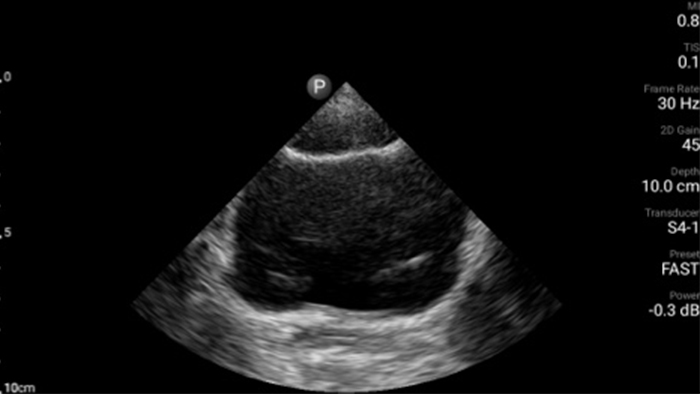

• Rozszerzony zakres częstotliwości roboczej od 4 do 1 MHz • Obrazowanie 2D, kolorowy Doppler, tryb M-mode, zaawansowana technika XRES oraz wielowymiarowe obrazowanie harmoniczne • Obrazowanie w wysokiej rozdzielczości do badań jamy brzusznej i serca: optymalizacja predefiniowanych ustawień badań serca, położniczo-ginekologicznych, płuc, jamy brzusznej oraz FAST.

Od ukazania subtelnych detali obrazu do znakomitego odwzorowania tkanek pod różnymi kątami — system Lumify może pomóc w pewniejszym podejmowaniu decyzji klinicznych tu i teraz zarówno w przypadku wstępnej diagnostyki pacjenta, jak i podczas jego leczenia.